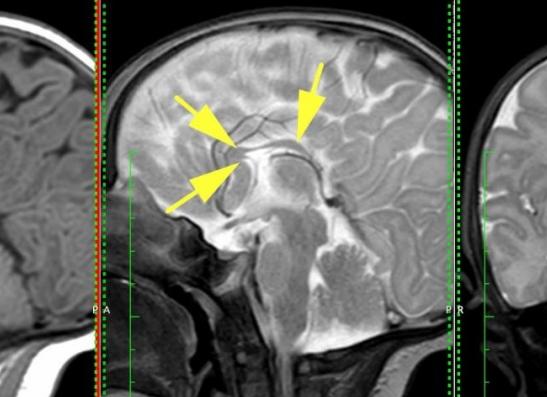

Диагностируют болезнь путем сканирования головного мозга

Диагностика заболевания может быть выявлена при выполнении процедуры сканирования головного мозга.

Проведение пренатальной диагностики такой аномалии как агенезия мозолистого тела сопряжена с большими трудностями. Чаще всего диагностируют аномалию на этапе второго-третьего триместра беременности.

В качестве основного метода используют метод эхографии, находят применение также процедуры МРТ, УЗИ.

Проведение процедуры эхографии в пренатальный период позволяет диагностировать далеко не все случаи заболевания, в том числе из-за особенностей предлежания плода.

Кроме того, при частичной агенезии обнаружить дефект еще более затруднительно.

Для получения полной картины обследования в случае подозрения на наличие аномалии необходимо выполнять кариотипирование, а также тщательный ультразвуковой анализ, диагностики с использованием магнитно-резонансной томографии.

Сочетание различных современных методов обследования позволяет с большей достоверностью диагностировать случаи агенезии мозолистого тела в пренатальный период.